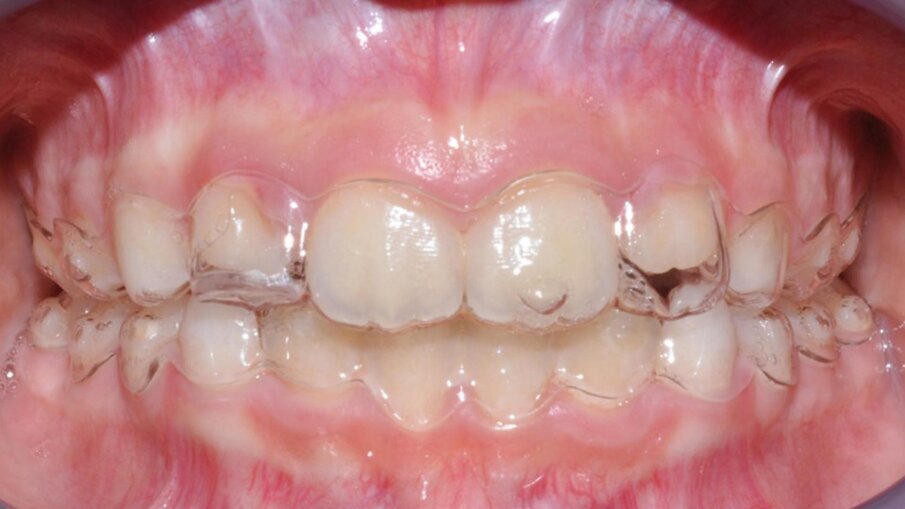

Il paziente di 7 anni e 6 mesi presentava una malocclusione di I classe scheletrica in prima fase di dentizione mista, con permanenza in arcata dei due incisivi laterali superiori decidui caratterizzata da affollamento severo delle zone apicali2, diminuzione dei diametri trasversi superiori con mesiorotazione dei primi molari superiori, forma ogivale dell’arcata inferiore con affollamento dentale, accentuazione della curva di Spee con estrusione degli incisivi inferiori, disestetismi posizionali e morfologici del gruppo anteriore legati a un’alterata eruzione passiva ritardata3 in arcata superiore e all’estrusione degli incisivi inferiori e deviazione delle linee mediane (Fig. 1).

Fig. 1_Fotografie occlusali pretrattamento.